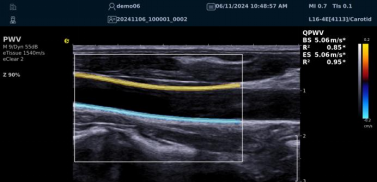

QPWV 彩色脉搏波传导速度定量技术

QPWV 技术是3377体育医疗的极速脉搏波速度测量技术,对脑卒中诊疗优势明显:

image.png

? 可进行动脉壁运动速度 - 时间彩色成像,直接测量单点脉搏波传导速度及相关参数(如 BSES 时的速度及标准差)。

? 能在血管内中膜增厚前的内皮功能不全阶段检测异常,对早期动脉硬化评估极具临床价值。

? 操作简单直接,无需附加设备,影响因素少,检测快速、重复性和稳定性高。